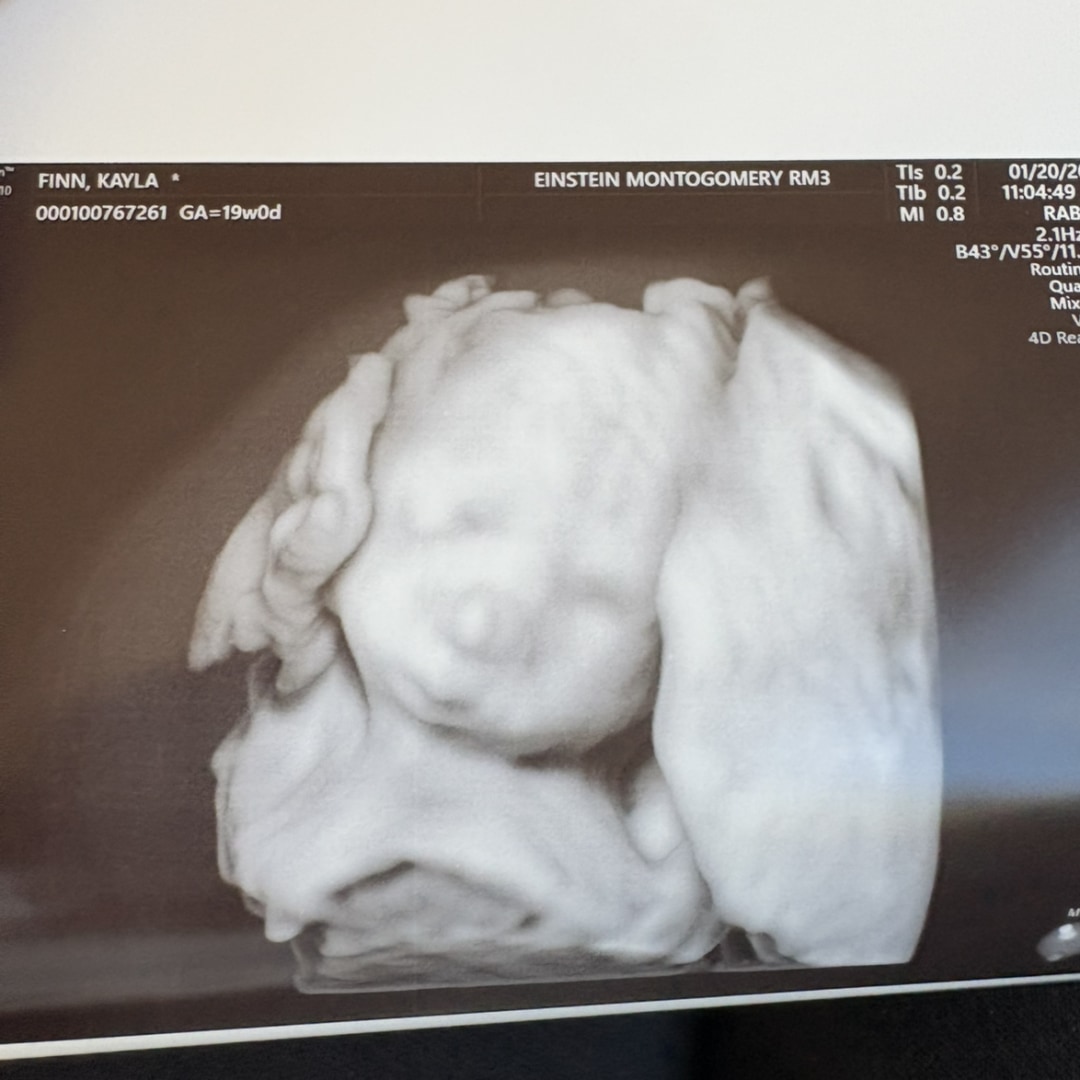

Our sweet little soccer player

Kayla & Mike Finn

Collegeville, PA

June 1, 2026